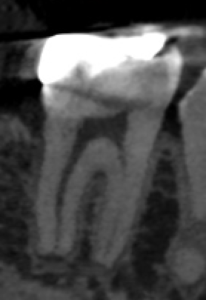

#31 Dに直覆したような痕跡がある。

遠心根管だが、

遠心舌側は既に露髄しているだろう。

これが、痛みの原因だと思われる。

術後にPA, CBCTを撮影した。